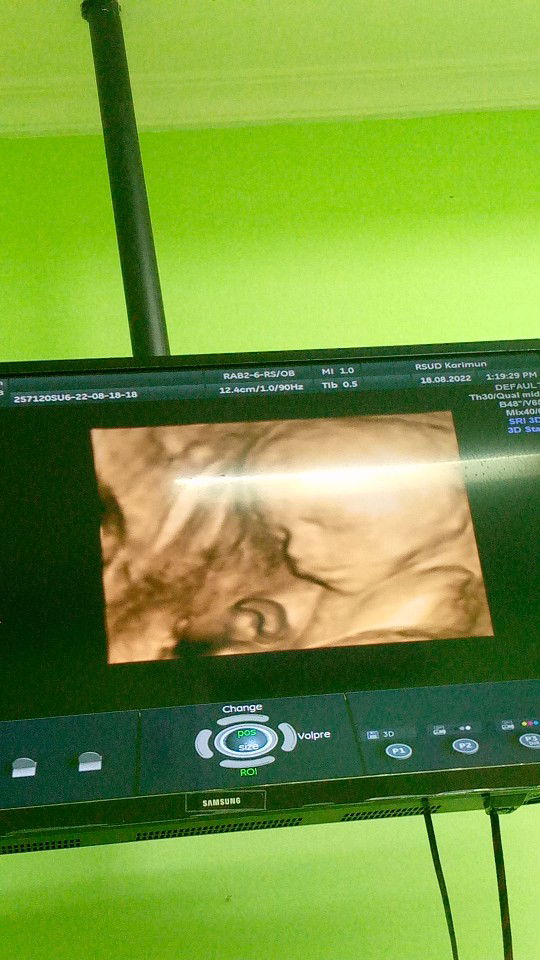

Kemarin USG 25 Minggu BB janin uda 1800 Gr . Itu normal apa kekecilan yaa Bun ? #bantusharing #seriusnanya

memang 1.800 Bun kata dokternya bukan 800 gram